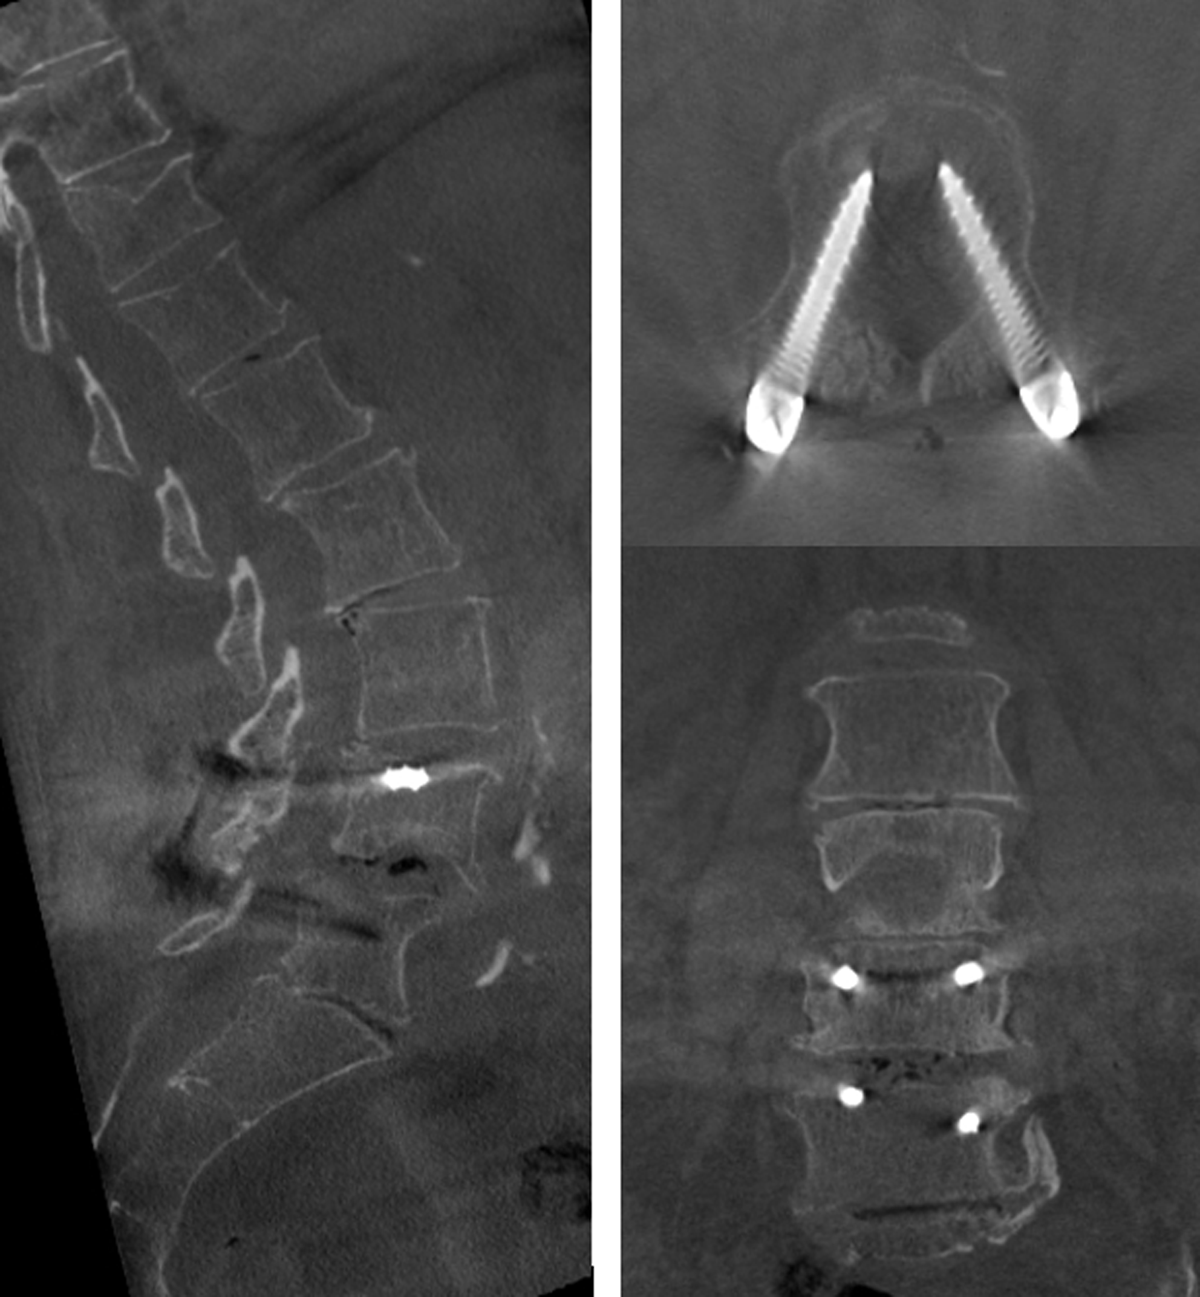

With this larger gantry and higher tube voltage (120 kV), large joints and body parts can be examined. The high-spatial resolution of bony architecture leads to a very good evaluation of fusion material in cervical and lumbar spine (Figure 1). High-spatial resolution images of cartilage surface after intra-articular contrast injection, already shown very useful in other joints such as the wrist [78], can now be obtained in the shoulder joint (Figure 2). The availability of fluoroscopy makes it possible to perform the contrast injection while the patient is installed for the scan, keeping the time between injection and scan to a minimum.

Figure 1

New techniques with image stitching make it now possible to scan a large FOV, up to 29 (x-y axis) × 56 cm (z-axis) and 17 × 62 cm. For example, the whole lumbar spine or a fracture of a large bone can be fully visualized, with a superior bone detail as compared to MDCT (Figure 3). Different combinations of small FOV and different dose settings make help minimizing dose exposure whilst imaging smaller bones and children.

Figure 3